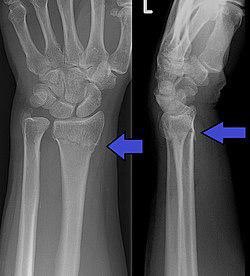

⁃ صورتين من الأشعة السينية (X-ray) في أغلب الحالات، أما في بعض الحالات المعقدة مثل كسور داخل المفاصل قد يحتاج التشخيص إلى الأشعة المقطعية (CT Scan).

⁃ كسر كولِس (Colles’ Fracture): يدعى هذا الكسر أحيانًا بتشوّه ظهر الشوكة أو تشوّه الحربة بسبب الشكل الذي يأخذه مقدم الساعد.

⁃ كسر سميث (Smith Fracture): المعروف بكسر كولِس العكسي، يحدث نتيجة السقوط على رسغ مثني.